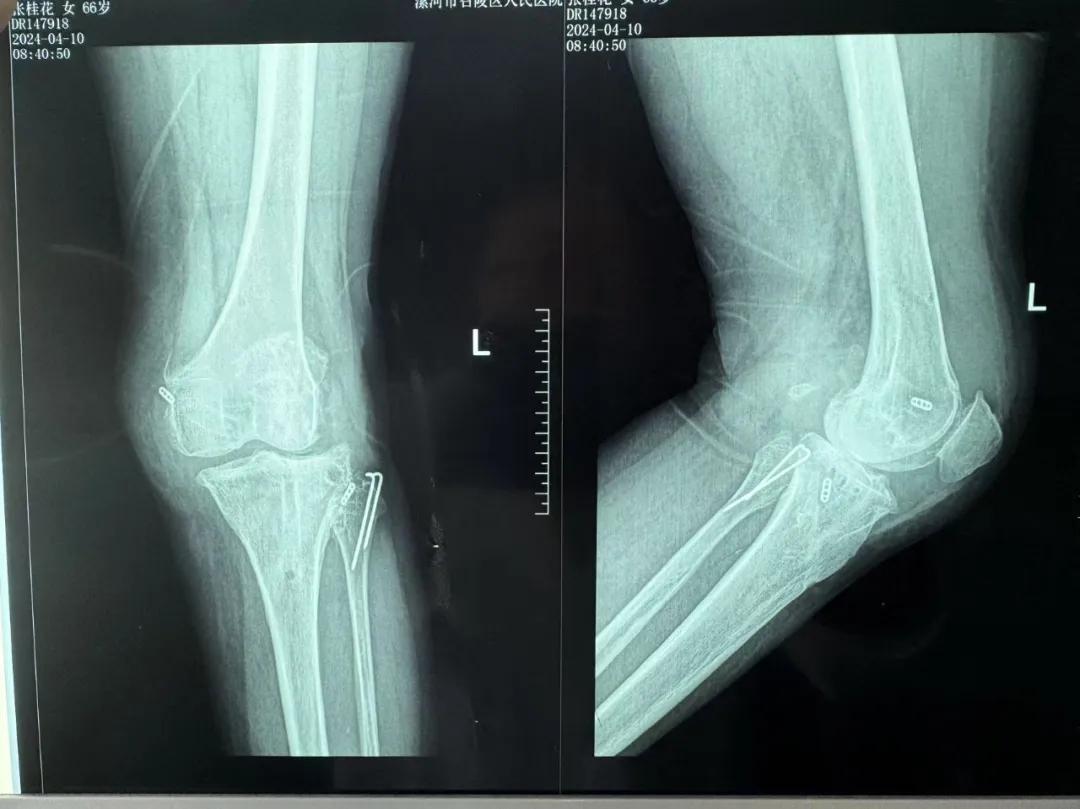

患者來院后,漯河市骨科醫(yī)院(漯河醫(yī)專二附院、漯河市立醫(yī)院)主治醫(yī)師康樂便成了她的管床醫(yī)生。在經(jīng)過詳細(xì)的術(shù)前診斷與檢查后,關(guān)節(jié)外科主任李付彬組織科室團(tuán)隊(duì)針對(duì)患者的診斷情況進(jìn)行術(shù)前討論——患者為重度膝關(guān)節(jié)骨關(guān)節(jié)炎,需進(jìn)行人工關(guān)節(jié)置換。但術(shù)前的評(píng)估結(jié)果顯示:患者膝關(guān)節(jié)側(cè)方不穩(wěn)定,單純行初次表面膝關(guān)節(jié)置換,術(shù)后仍會(huì)存在側(cè)方不穩(wěn)的情況,會(huì)影響術(shù)后效果以及假體使用年限,不僅無法完全恢復(fù)膝關(guān)節(jié)功能,還會(huì)加重患者的經(jīng)濟(jì)負(fù)擔(dān)。

為了盡可能給患者帶來更好的治療效果,減輕其經(jīng)濟(jì)負(fù)擔(dān),經(jīng)綜合評(píng)估后,李付彬主任帶領(lǐng)團(tuán)隊(duì)制定了最終的手術(shù)方案——決定使用髁限制性膝關(guān)節(jié)假體(LCCK)置換膝關(guān)節(jié)。作為解決患者病痛的最優(yōu)方案,這項(xiàng)手術(shù)具體實(shí)施的難度并不小,需要在術(shù)中根據(jù)截骨情況進(jìn)行多次評(píng)估和實(shí)時(shí)調(diào)整,這就要求主刀醫(yī)生不僅要具備過硬的專業(yè)技術(shù)與能力,還要能夠結(jié)合自身的經(jīng)驗(yàn)準(zhǔn)確判斷、精準(zhǔn)操作。

手術(shù)過程中,關(guān)節(jié)外科團(tuán)隊(duì)為患者進(jìn)行了標(biāo)準(zhǔn)截骨,經(jīng)過評(píng)估,患者膝關(guān)節(jié)仍存在膝關(guān)節(jié)側(cè)方不穩(wěn)定,便按照原定手術(shù)計(jì)劃使用LCCK假體進(jìn)行了膝關(guān)節(jié)置換。經(jīng)過再次評(píng)估,患者膝關(guān)節(jié)穩(wěn)定性恢復(fù),下肢力線正常,這臺(tái)高難度的LCCK膝關(guān)節(jié)置換手術(shù)在一小時(shí)內(nèi)便順利完成!術(shù)后第二天,患者就能夠自主下床負(fù)重活動(dòng),功能恢復(fù)良好。